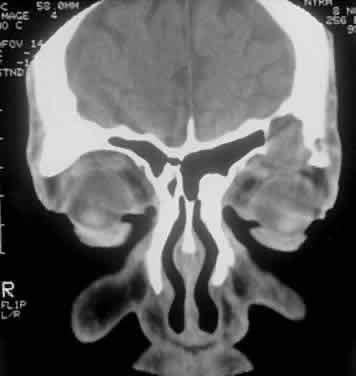

Multiple myeloma is the prototypic systemic plasma cell tumor that occurs in the elderly, more commonly men, with multiple masses of plasma cells disseminated throughout the skeletal system and soft tissue.7 Extraskeletal metastases occur in 70% of cases, either by hematogenous spread or by direct extension. Morbidity and mortality stem from bone marrow invasion with resultant anemia, infiltration of visceral organs, amyloid deposition, and secretion of immunoglobulin and osteoclast-activation factors. Multiple myeloma can metastasize to the kidney, adrenal gland, heart, and liver and can cause punched-out lesions of the skull and vertebral fractures. Mean survival is 3 years with chemotherapy, and the presence of Bence Jones proteins worsens prognosis. An aggressive variant of multiple myeloma is disseminated nonosteolytic myelomatosis, which progresses rapidly, involving bone marrow and soft tissues without radiographic changes. Orbital soft tissue metastasis with orbital bone destruction has been noted in a series to occur in 5 in 2000 cases, and invasion of orbital bone is even less common94–98 (Fig. 15). Amyloid deposition into the extraocular muscles can occur.99

Fig. 15. A 48-year-old Indian man with known systemic multiple myeloma and subsequent plasmacytoma involving the left orbit with lateral orbital wall destruction (A), as evident on axial CT scan (B).